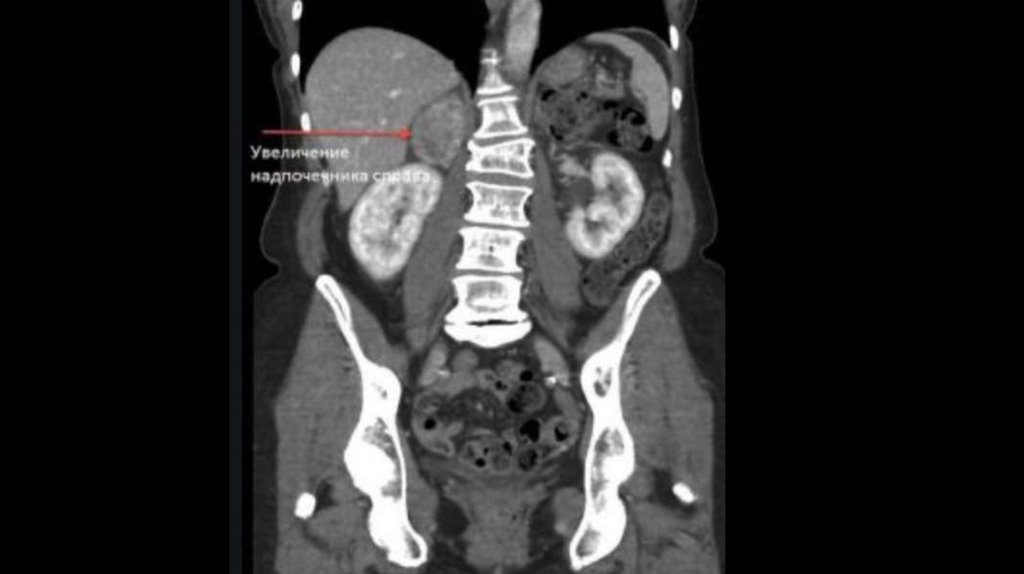

20. МРТ/КТ

• ◊ При МРТ в сочетании с контрастированием гипофиза

(гадолиний) аденома выявляется в 80% случаев.

• ◊ Однако следует иметь в виду, что аденома гипофиза выявляется

у 10% лиц без нарушения функции гипофиза, поэтому

биохимические исследования гормонов имеют решающее

значение.

• ◊ В случае подозрения на АКТГ-независимый синдром Иценко –

Кушинга при МРТ/КТ в надпочечниках можно выявить

характерные морфологические изменения.